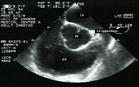

診斷:X 線、內鏡及活組織檢查可確診。

其他輔助檢查:X 線、內鏡及活組織檢查。